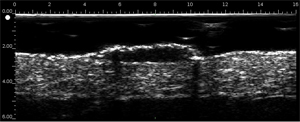

Le DERMCUP permet d’acquérir, de façon non invasive, des coupes verticales de la peau in vivo.

Le derme est échogène. Les échos proviennent du réseau de fibres collagènes et de fibres élastiques. Par rapport au derme, les lésions (tumeurs, kystes, angiomes…) apparaissent comme des zones hypoéchogènes.